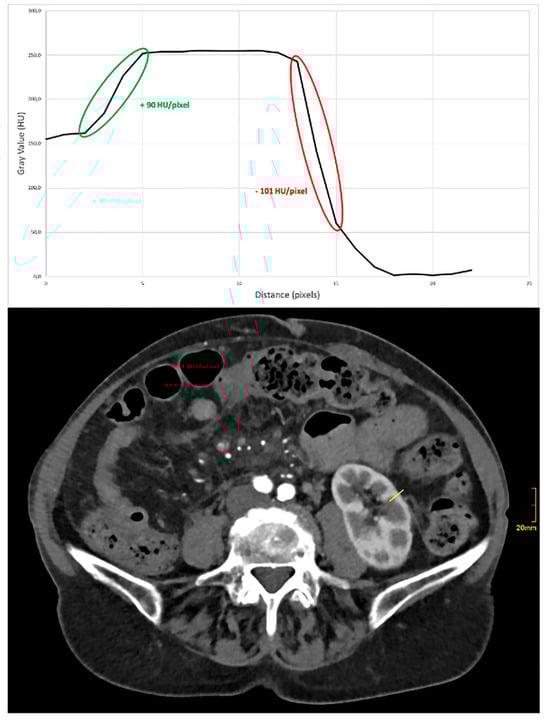

Furthermore, another non-reader radiologist measured objective sharpness of the kidney parenchyma using line-density profiles. A 1 cm line was drawn, which covered the renal cortex, medulla, and adjacent fatty tissue. Maximum and minimum HU values, as well as the distance between those values, were recorded and the slope (increase or decrease) was calculated using ImageJ (Version 1.54j), as previously reported [22]. For the purpose of this analysis, a representative slice with homogeneous kidney parenchyma and surrounding fat was chosen. Caution was undertaken, not to measure into any lesions or adjacent structures.

3.4. Assessment of Image Sharpness

Image sharpness, expressed as the steepness of the CT number gradient of the renal medulla:renal cortex and renal cortex:renal fat, respectively, was higher in the group with the thinner slice thickness (mean HU [HU/mm] for 0.4 mm 39.1 ± 12.7 vs. 31.2 ± 9.0 vs. 35.6 ± 9.6 for 1.0 mm and 3.0 mm, respectively, for medulla:cortex, and −86.0 ± 29.9 vs. −75.9 ± 22.5 vs. −80.6 ± 22.6, respectively, for cortex:fat). The impact of various kernels on image sharpness was less pronounced (mean HU Br40 vs. Br44 vs. Br 48 vs. Br56: 35.8 ± 11.8 vs. 34.8 ± 10.8 vs. 33.9 ± 10.6 vs. 36.7 ± 10.9, respectively, for medulla:cortex and −79.6 ± 24.4 vs. −84.3 ± 23.2 vs. −82.3 ± 32.5 vs. −77.0 ± 20.6, respectively, for cortex:fat). Regardless, there was no statistical difference between either variations of slice thicknesses or kernels (p > 0.05). For an example of a line density profile, see below Figure 4.

Figure 4. Example of a line density profile for objective analysis of image sharpness. The ascending (green) part of the slope refers to the change of density between renal medulla and cortex, while the descending (red) slope refers to the density change between renal cortex and perirenal fat. Steeper curves correlate with a higher degree of image sharpness.